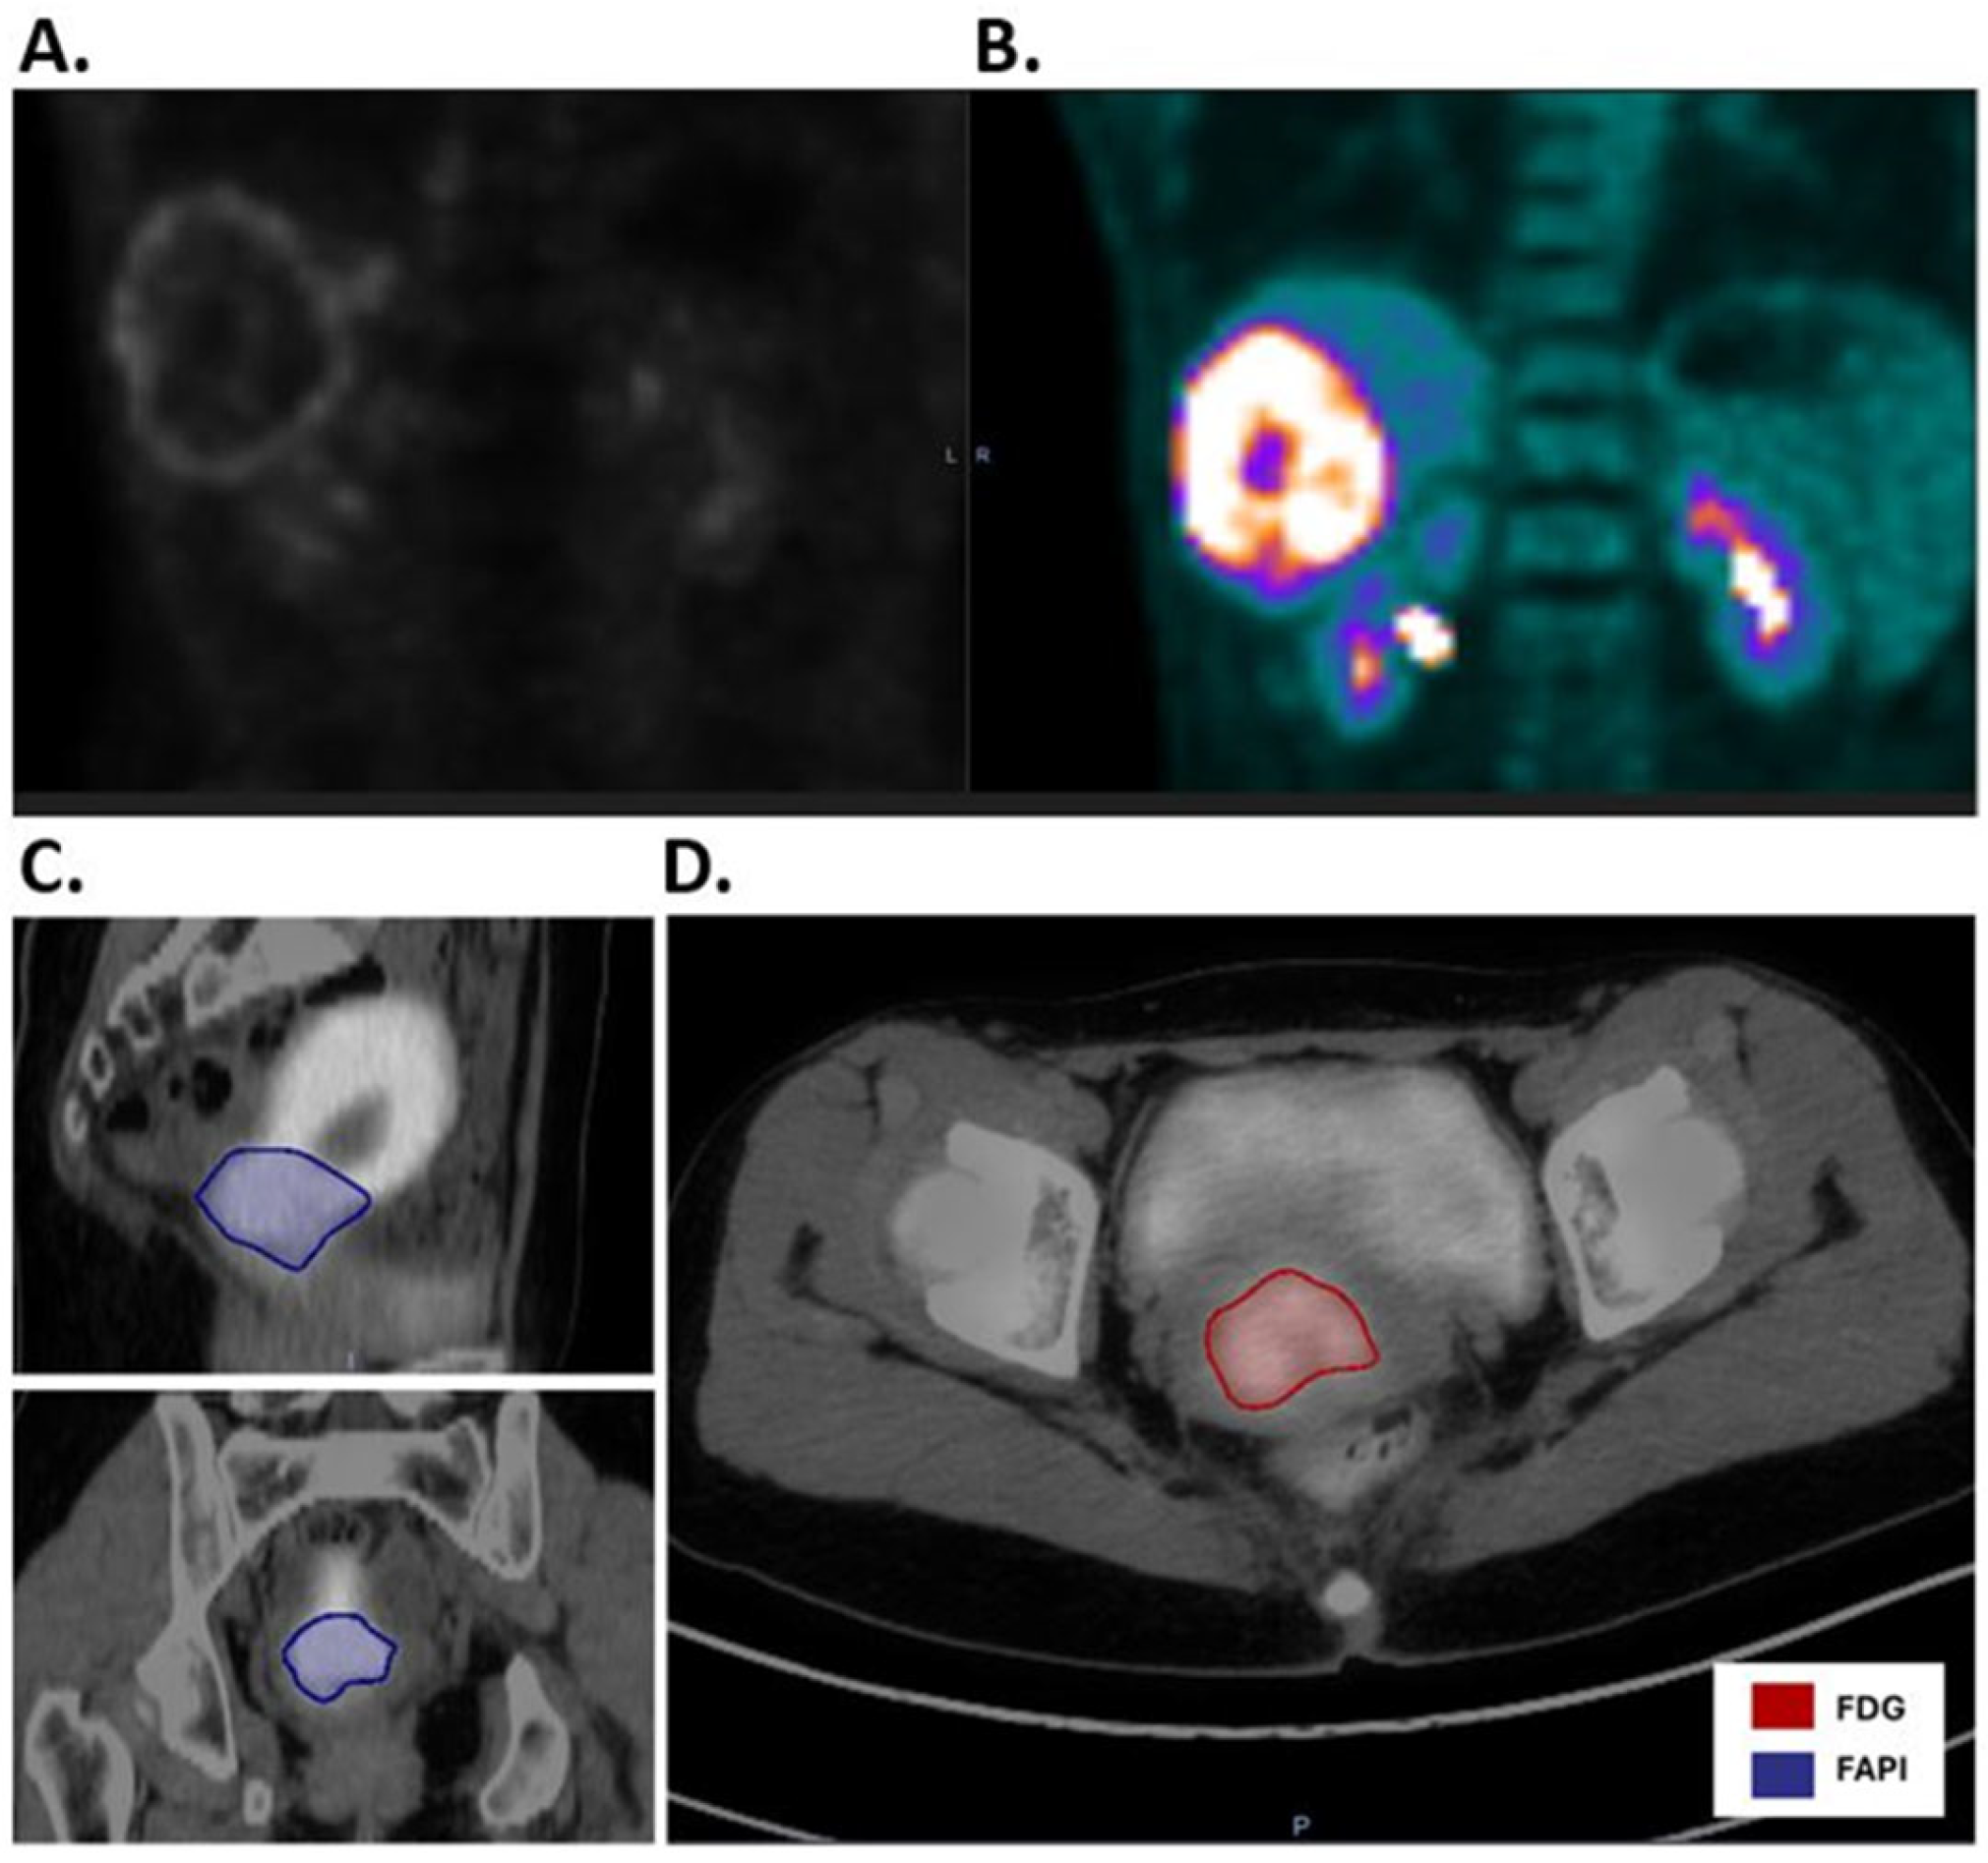

3.2.4. Cervical Cancer